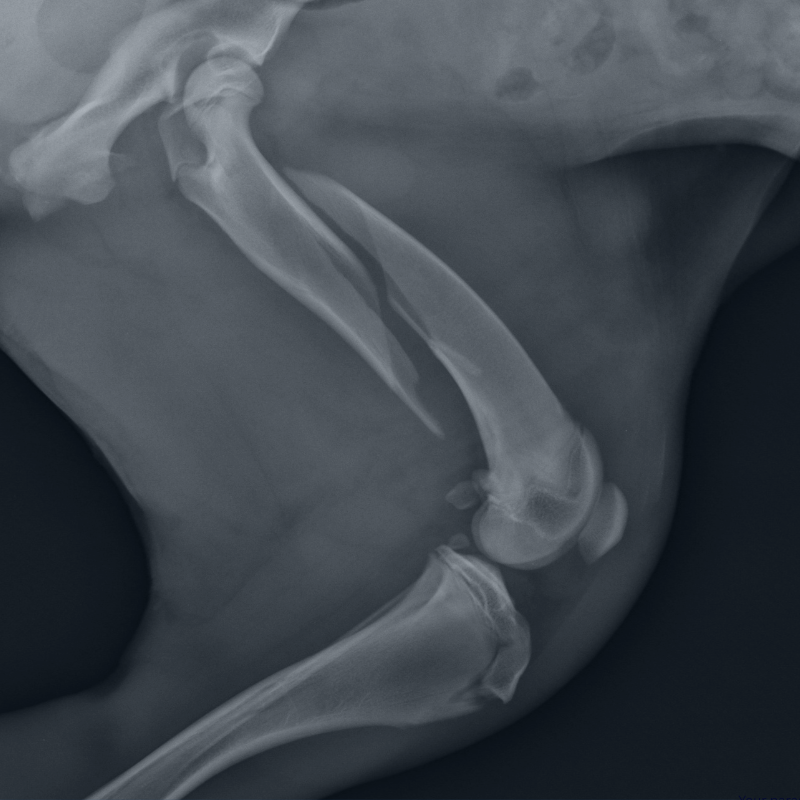

Avascular necrosis (AVN), also known as aseptic osteonecrosis, occurs when blood flow to a bone is disrupted, leading to oxygen deprivation and the eventual death of bone tissue. The most commonly affected site is the femoral head, though AVN can also involve the femoral condyles, humeral head, talus, calcaneus, or navicular bones.

Avascular necrosis occurs when blood supply to bone tissue is reduced or interrupted. Without sufficient oxygen delivery, bone cells fail to maintain structural integrity, leading to progressive tissue compromise. Early AVN is a metabolic failure, not merely a structural issue.

Once structural collapse begins, regenerative options become limited. HBOT is most effective when introduced before significant bone deformation occurs, allowing oxygen-driven repair mechanisms to stabilize the femoral head and preserve joint function.